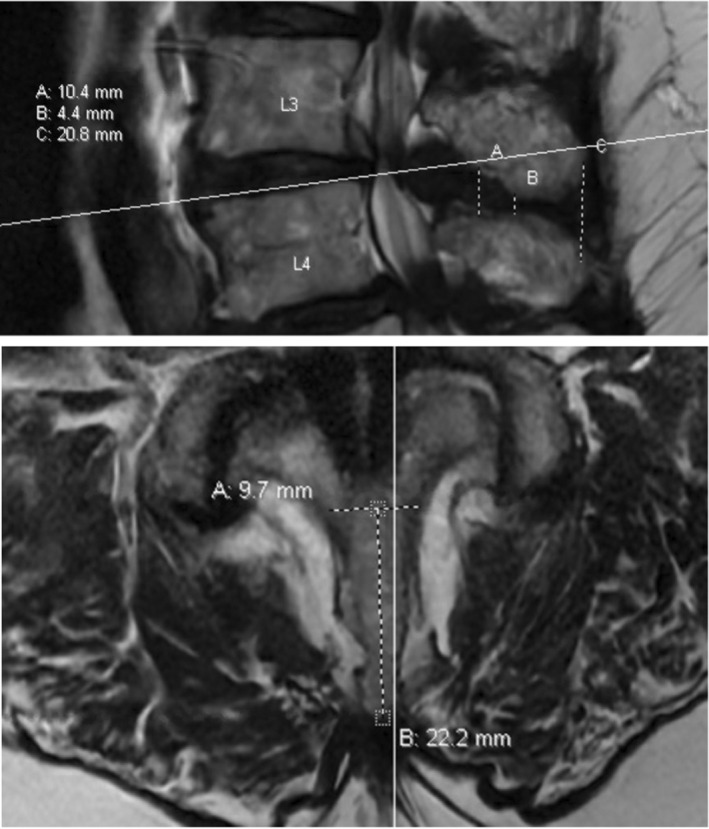

Methods: Patients who underwent Vertiflex ISS with Lumbar Spinal Stenosis (LSS) and a preoperative MRI available in picture archiving and communication system (PACS) between January 2013 to February 2023 were identified retrospectively from the University of Chicago Medical Center Database. An experienced board-certified pain specialist and well-trained 2nd-year medical student independently performed measurements of the interspinous space where Vertiflex ISSs of various sizes are inserted. MRI measurements were taken blinded to intraoperative measurement and ISS implant size used in the procedure. Pearson's correlation, paired T-test, intraclass correlation coefficients (ICC), absolute agreement, and 2-way random effects model were used to determine the relationships between MRI, intraoperative measurement, and ISS size.

Results: A total of 79 patients who underwent the Vertiflex ISS procedure were included in the study. Median Vertiflex ISS size was 10 mm (10-12), mean intraoperative measurement was 11.40 mm (±1.23), and mean MRI measurement was 11.24 mm (±1.44). Mean differences were not significant in intraoperative and MRI measurements (p = 0.271). Pearson's correlation between ISS size and intraoperative measurement was 0.807 (p < 0.001), representing the current best practice model. Pearson's correlation was 0.668 (p < 0.001) between MRI measurement and ISS size and 0.542 (p < 0.001) between MRI and intraoperative measurement. ICC showed good agreement and moderate reliability (0.698) between intraoperative and MRI measurements. Observer interrater ICC agreement of the MRI interspinous space measurement was 0.95 (p < 0.001).